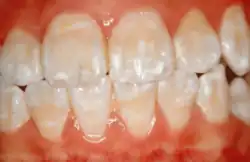

Enamel hypocalcification is characterized by the presence of white spots or streaks on the teeth due to reduced mineral content,[34] posing both cosmetic concerns and potential structural weaknesses. White spots can also be seen in patients. As the enamel undergoes demineralization, it becomes thinner, often leading to yellow or brown discoloration. The severity of this discoloration can range from mild yellowing to more pronounced brown staining, reflecting the extent of enamel loss.[7] This compromised enamel layer can also heighten tooth sensitivity to temperature changes and sugary foods, as external stimuli more easily reach the pulp, causing discomfort. Additionally, individuals with enamel hypocalcification experience a higher incidence of dental caries, as the weakened enamel provides less resistance to acid produced by oral bacteria.[19]

Clinical manifestations

Enamel hypocalcification is characterized by visible defects in the enamel, often manifesting as white spot lesions or brown discolorations.[35] In cases such as dental fluorosis, this may include mottled patterns on the enamel surface which vary in appearance and extent based on the severity of the condition.[36] In advanced cases, the mottled appearance of the enamel can expose the underlying dentin, creating an uneven and sometimes porous surface. Though the matrix of the enamel initially forms to a typical thickness, the mineralization or calcification process is incomplete or deficient, leading to softer and structurally compromised enamel.[35]